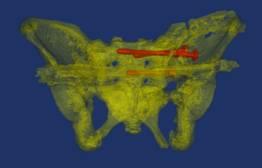

骨盆术前三维模型和模拟复位--正位前面观

骨盆术前三维模型和模拟复位--正位后面观